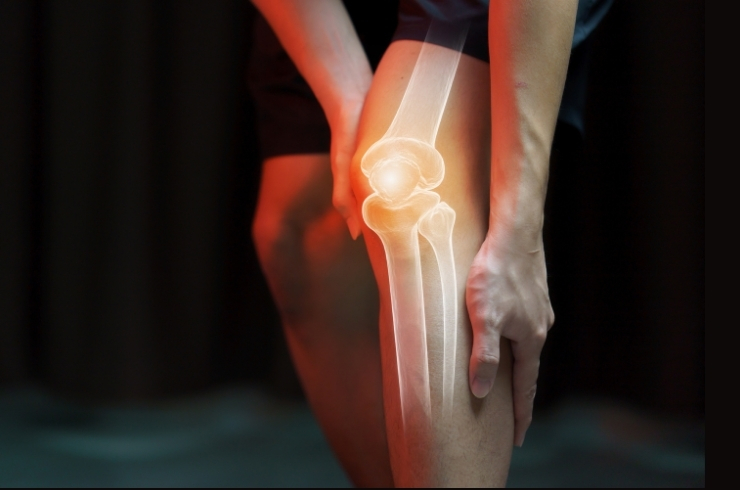

Advanced treatment for bone, joint, and spine disorders including joint replacement and trauma care.